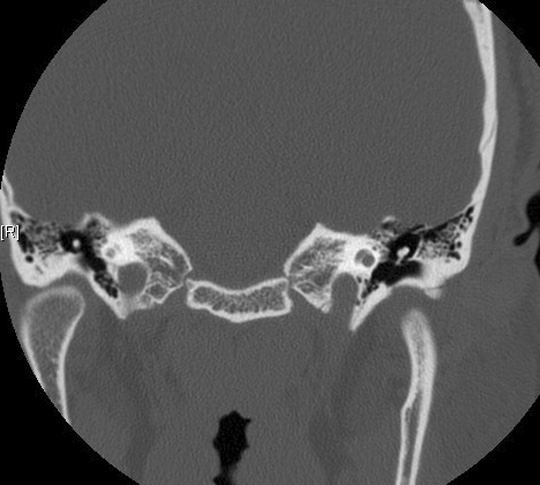

Identify the malleus and cochlea. Click the image for labeling.